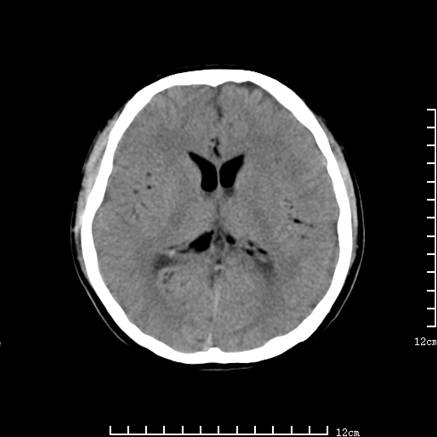

以下是引用jiajie在2008-9-5 22:25:00的发言:[br]男,22岁,头痛1月余。脑室、脑池内病变ct值约-120hu。[br][br]双侧侧脑室内低密度影充填,出现脑脊液脂肪平面,脑池内亦可见弥散分布的斑点状低密度影,脑室脑池未见明显扩大。[br]考虑胆脂瘤破裂后内容物进入脑脊液。